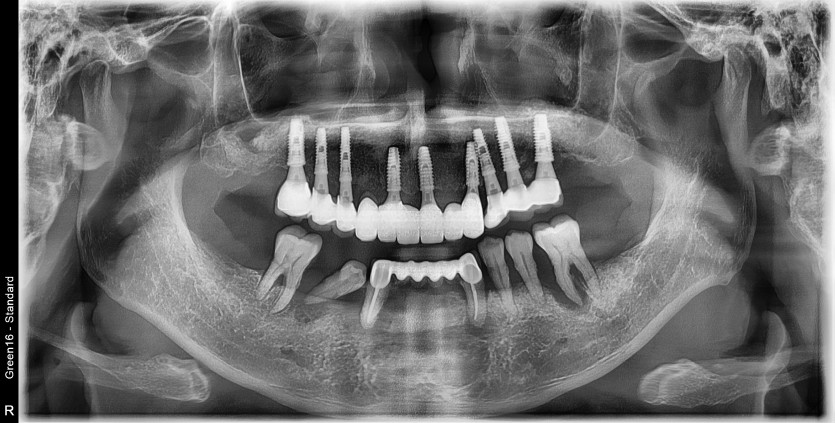

만 61세 하악 전체 임플란트 증례

하악 전체 임플란트 증례입니다.

8개의 임플란트로 완성하였습니다.